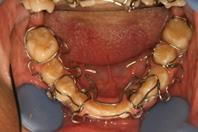

Маилян 2. Конструкции ортодонтических аппаратов для исправление зубоальвеолярных дуг представляют установленные на отдельных зубах и/или их группах элементы крепления в виде опорноудерживающих металлических проволочных каркасов выполненных с рассредоточено установленными по высоте коронок зубов деталями и соединенных между собой лингвальными (дугами) и/или вестибулярными пружинами (см. Фиг1, 2, 3). Для обеспечения сагиттально-трансверсальных перемещений отдельных боковых зубов или их групп опорно-удерживающие каркасы аппарата в области боковых сегментов с отдельными секторамии соединяются между собой вестибулярными или лингвальными пружинами (см. Фиг. 2, 3).

Фиг.2

До (М2-2)

После 6-и месяцнв  (М2-2)

После 9-и месяцев  (М2-2)